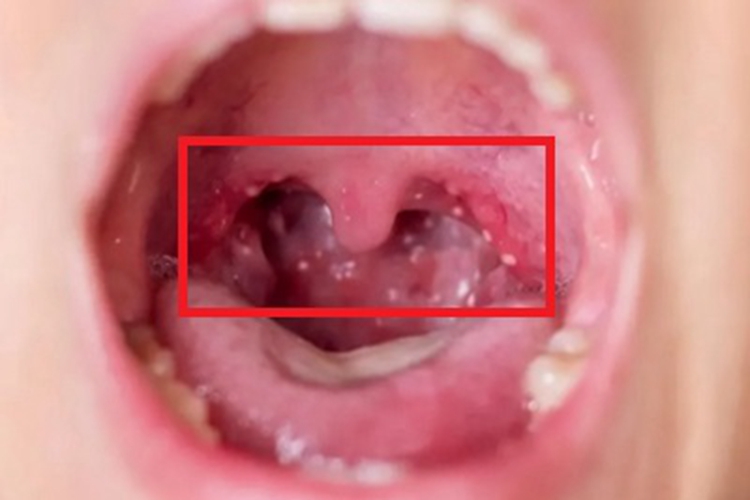

疱疹性咽峡炎患者张口时可见咽喉部有很多灰白色的小水疱,直径不等,伴有疼痛感。

疱疹性咽峡炎患者检查时,可见咽喉部位充血、水肿,黏膜上出现数个灰白色丘疱疹或小水疱,直径不等,周围绕以红晕。2-3日后,红晕可加剧并扩大,疱疹破溃形成溃疡,一般1周左右愈合。